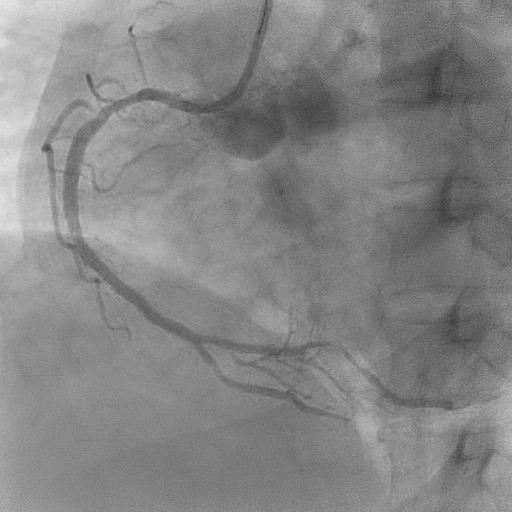

The coronary angiogram showed a right-dominant system. The right coronary artery (RCA) had a patent mid stent with mild diffuse disease and good TIMI 3 flow. The Quantitative Flow Ratio (QFR) was 0.97, indicating preserved physiological flow. A dual LAD anatomy was noted with significant bifurcation lesions (Medina 1,1,1) involving the mid first LAD and the ostial to mid second LAD. The non-dominant left circumflex artery and left main stem were normal.